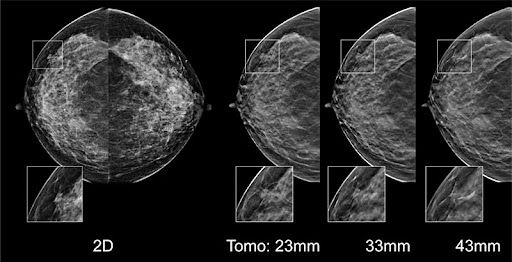

AI-fueled mammography triage software from DeepHealth wins 510(k).

Combination also leads to a reduction in the false-negative rate.

Training sets from different vendors may be required to ensure scanner-specific sensitivity.